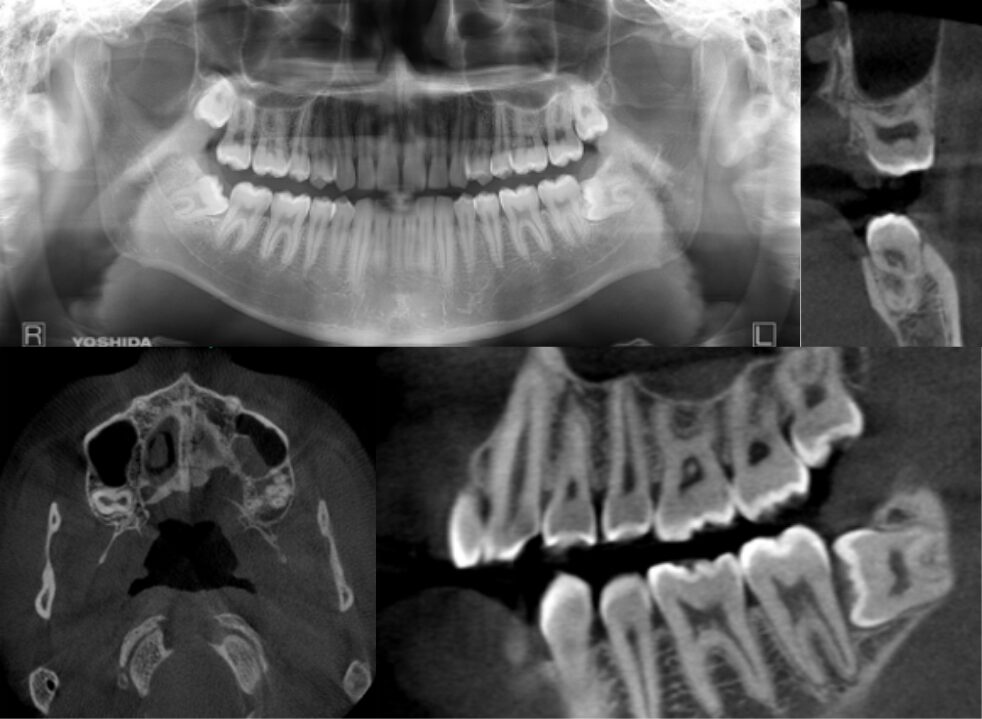

水平断にて4根 冠状断・矢状断にて根の離開、彎曲が大きく特異的な形態の症例

| 患者情報 | 24歳 男性 |

| 手術時間 | 3分 |

| 治療内容 | 親知らず抜歯 |